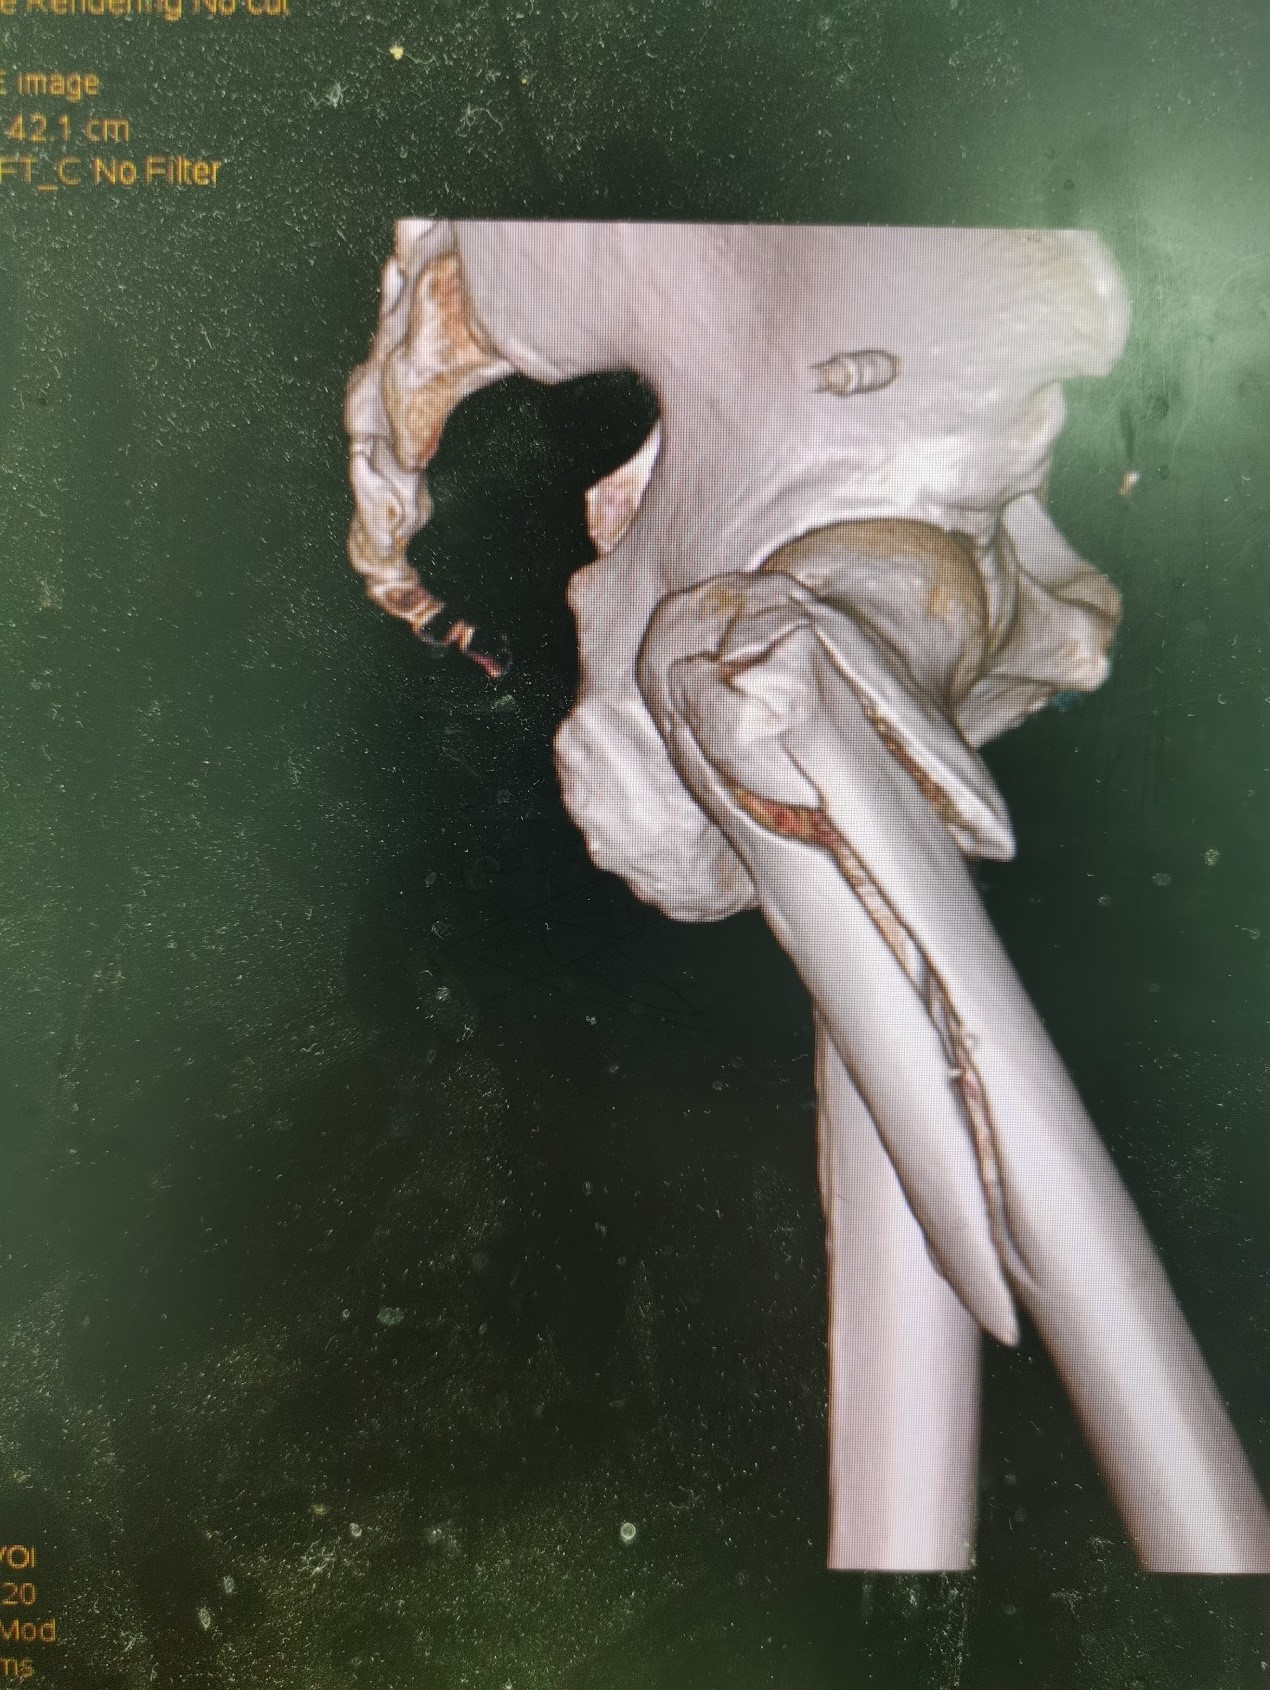

案例二:51岁男性意外摔伤

患者情况:吴先生因路面湿滑不慎摔倒,导致右髋部疼痛并活动受限,经检查确诊为股骨粗隆间骨折。

治疗难点:

1.骨折部位解剖重建的准确性;

2.内固定材料的选择及固定强度的保障。